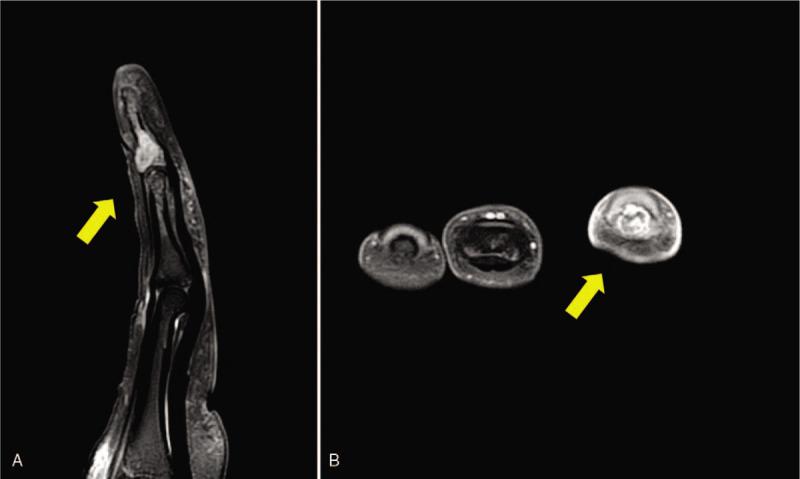

Magnetic resonance imaging revealed an eccentrically located lesion expanding to the cortex, with a high signal intensity at T2 weighted image, suggesting pathologic fracture.

磁共振成像显示一个偏心性病变向皮质扩展,在T2加权像上呈高信号强度,提示病理性骨折。